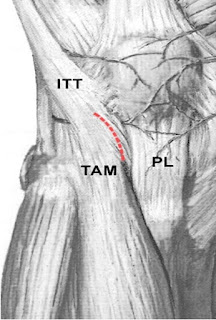

Use of proximal tibia as a donor site has been applied in jawbone reconstruction since the 1990s. Catone and colleagues described a U-shaped incision made on the iliotibial tract during tibial cancellous bone procurement for maxillofacial reconstruction in 1992. We used a curvilinear incision on the iliotibial tract in lateral approach in our tibial

cancellous bone harvesting procedure.

Eighty consecutive jawbone reconstructions utilizing autogenous tibial cancellous bone grafts in 78 patients from March 1998 through March 2008 were reviewed. The patient group consisted of 45 males and 33 females, ages 18 to 76 (average age 36.1 1 12.3).Minimal postoperative follow-up period was 3 months. Unlike the traditional U-shaped trapdoor incision on the iliotibial tract, our curvilinear incision was made almost parallel to the fibers of that tract.

The modified incision on the iliotibial tract allowed access to obtain an equally good bone volume from the lateral aspect of the proximal tibia, and it rendered wound closure much easier than the procuring techniques described in the earlier literature.

KEY WORDS: bone graft, Gerdy’s tubercle, iliotibial tract, jaw reconstruction, tibia